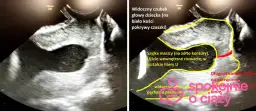

USG jest często pierwszym wyborem w diagnostyce zrostów. Ta bezbolesna i nieinwazyjna metoda pozwala na wstępną ocenę struktur miednicy. Może uwidocznić nieprawidłowości w położeniu narządów oraz zmiany w ich ruchomości. USG jest szczególnie przydatne w wykrywaniu zrostów w obrębie macicy i jajników.

Laparoskopia, choć bardziej inwazyjna, oferuje dokładniejszy obraz. Pozwala na bezpośrednią wizualizację zrostów i ocenę ich rozległości. Podczas tego zabiegu lekarz może nie tylko zdiagnozować problem, ale także podjąć próbę usunięcia zrostów. Jest to szczególnie cenne w przypadkach, gdy zrosty są rozległe lub powodują znaczne dolegliwości.